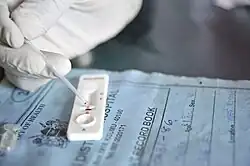

| Método de diagnóstico | Análises ao sangue, testes de diagnóstico rápido de malária[1] |

A malária é geralmente confirmada através de exame microscópico de esfregaços ou através de testes de diagnóstico rápido (DRT) baseados na deteção de antígenos.[44][45] A microscopia é o método mais comum na deteção do parasita.[46] No entanto, apesar do seu uso generalizado, o diagnóstico por microscopia tem duas desvantagens: muitos locais, sobretudo em meios rurais, não têm equipamento para a realização do exame e a precisão dos resultados depende da destreza do examinador e da quantidade de parasitas no sangue. A sensibilidade dos esfregaços varia entre 75–90% em condições normais, podendo diminuir até 50%. Os testes de diagnóstico rápido disponíveis são mais precisos a determinar a presença de parasitas da malária do que a análise microscópica, embora a sua sensibilidade e especificidade dependam do fabricante e não sejam capazes de determinar o número de parasitas.[46]

Em regiões onde estejam disponíveis análises de laboratório, deve-se suspeitar a presença de malária em qualquer paciente que manifeste sintomas e que tenha estado numa região onde a malária seja endémica. Em regiões onde não há capacidade de disponibilizar facilmente análise laboratorial, tem vindo a tornar-se rotina usar apenas o histórico de febre subjetiva como indicador de tratamento para malária – um diagnóstico presuntivo que assume que febre corresponde a malária, a não ser que haja prova em contrário. Uma desvantagem desta prática é o sobrediagnóstico de malária e a gestão inadequada de casos de febre sem relação com a malária, o que desperdiça recursos, diminui a confiança no sistema de saúde e aumenta a resistência a fármacos.[47] Embora tenham já sido desenvolvidos testes que têm por base a reação em cadeia da polimerase, não estão ainda difundidos pelas regiões onde a malária é endémica devido à sua complexidade.[5]